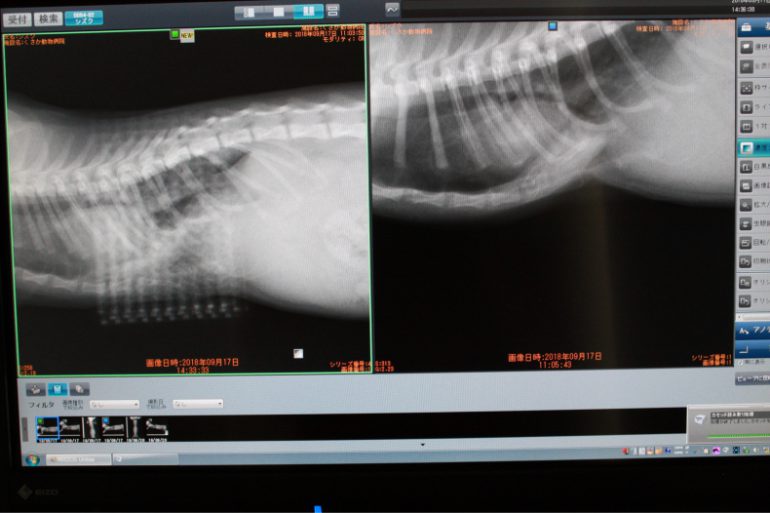

9/17は子猫さんの漏斗胸のオペがありました。

漏斗胸とはその名の通り、胸の前面が漏斗状に凹んでいる状態のお胸のことをいいます。

2枚目の写真と比べると、凹みが解消されているのがわかりますでしょうか?

オペ前とオペ後の写真です。